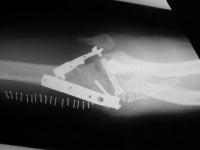

the operating surgeon decided to achieve stability with triple tension band fixation and bone graft:

Click for larger image

A triangle of tension bands was constructed using 1.6 and 2.0 mm pins, with the most distal pin transfixing all four distal fracture fragments. It would have been possible to add a wire through the center of the cannulated screw for an additional cerclage proximally, but this was not done because of concerns regarding corrosion at the titanium/stainless contact point. Although one pin appears to be within the old cannulated screw, it is not.